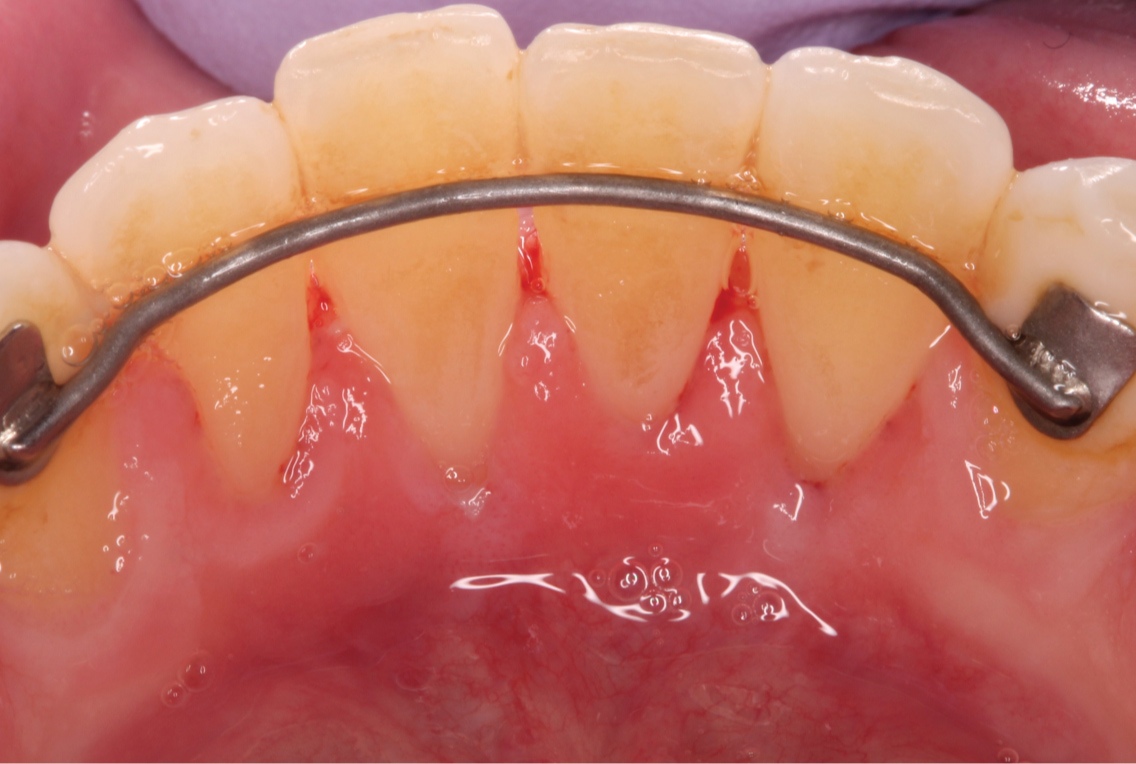

A sub-epithelial connective tissue graft (SCTG) was harvested using double parallel incisions as described by Harris on palate which was approximately 15 mm in length [9] (Figure 3). The donor site was closed by cross mattress stabilizing sutures using 4.0 chromic gut. Stabilizing sling suture was utilized to stabilize the connective tissue graft at the recipient site. The graft was tunneled laterally underneath adjacent papilla. 5.0 chromic sutures were used to sling the graft to #23 (Figure 4). After the SCTG was fixed by the sling sutures to the lingual exposed root surface at the CEJ, lateral margin of recession was approximated to cover the graft and closed with 6.0 polypropylene sutures. Simple interrupted loop sutures were utilized to close margins (Figure 5 and Figure 6). Only a minimal amount of connective tissue graft was exposed after approximating the lateral margins. Hemostasis was achieved with compression by a gauze.

Figure 6: Margins of the sub-periosteal tunnel approximated with 6.0 polypropylene sutures. View Figure 6

Postoperatively, the patient was prescribed 500 mg of amoxicillin TID for 7 days to prevent potential infection, 800 mg ibuprofen TID for pain management and twice daily rinse with 0.12% Chlorohexidine rinse for 2 weeks. Patient was instructed to not brush the surgical area for at least 2 weeks. Sutures were removed at 2 weeks after surgery and returned to regular post-operative oral hygiene at 1 month and regular dental recall appointments (Figure 7).